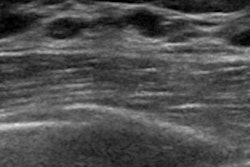

In ultrasound imaging, breast lesions are characterized according to the American College of Radiology's BI-RADS categories. But it can be difficult to classify breast lesions objectively in ultrasound images because of operator variability, Ciritsis and colleagues noted. Computer-aided diagnosis (CADx) systems have been used to support radiologists in their image interpretations, especially in the effort to distinguish between benign or suspicious lesions. But a deep-learning network could take this to another level.

The researchers used 1,019 breast ultrasound images from 582 patients to train the CNN. They then tested the neural network's accuracy on a dataset of 101 images that included 33 BI-RADS 2, 47 BI-RADS 3, and 21 BI-RADS 4-5 lesions; these images were also interpreted by two radiologist readers.